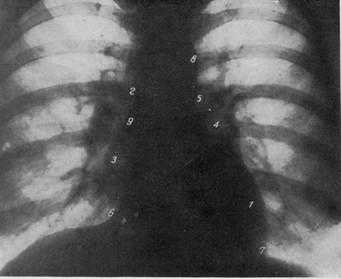

СХЕМА ПРОЕКЦИИ СЕРДЦА В ПЕРЕДНЕМ ПОЛОЖЕНИИ

1 — контур левого желудочка; 2—контур восходящей аорты; 3 — правый желудочек; 4 — контур правого предсердия; 5 — контур ушка левого предсердия; в — контур верхней полой иены; 7 — легочная артерия; 8 — срединная линия: 9 — позвоночник; 10—правый кардио-диафрагмальный угол; 11—левый кардио-диафрагмальный угол; 12 — дуга аорты; 13 — правый атриовазальный угол.

РЕНТГЕНОГРАММА НОРМАЛЬНОЙ ГРУДНОЙ КЛЕТКИ В ПЕРЕДНЕМ ПОЛОЖЕНИИ.

1 — дуга левого желудочка; 2 — дуга восходящей аорты; 3 — дуга правого предсердия; 4 — дуга ушка левого предсердия; 5 — дуга легочной артерии; 6 — правый кардио-диафрагмаль-ный угол; 7 — левый кардио-диафрагмальный угол; 8 — дуга аорты; 9 — правый атриовазалытый угол.